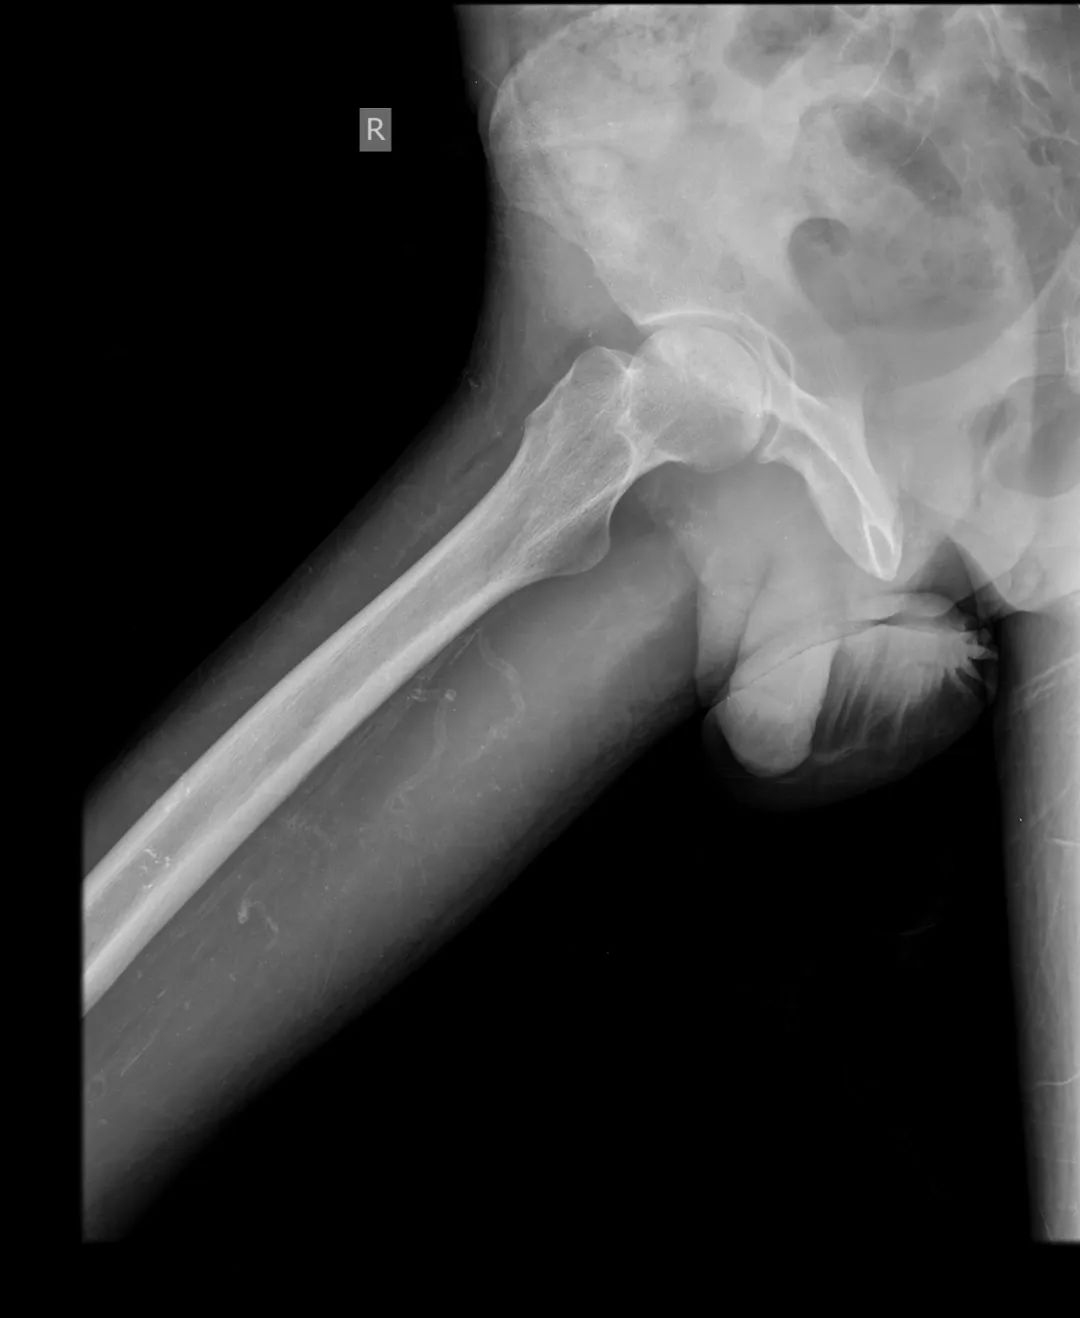

CASE M25 年轻男性,已知有类固醇治疗狼疮性肾炎史。伴有双侧髋关节疼痛和运动困难的抱怨。

不规则的透光区,代表软骨下囊变,与边缘硬化在两个股骨头。双股骨头呈线性软骨下骨折/断裂,伴有轻度塌陷/扁平。这些发现代表了双侧股骨头缺血性坏死。